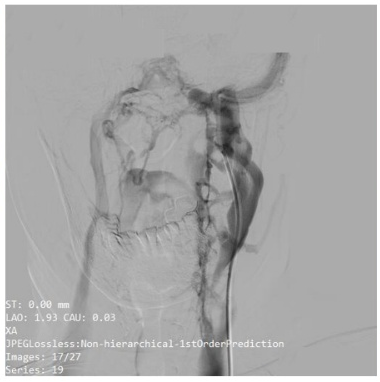

术前DSA

通过高分辨率颈静脉超声及CT静脉造影(CTV)检查,清晰显示患者左侧颈静脉存在明确的受压征象,这为脑内异常血流声的产生提供了解剖学依据。为确保诊断的精准无误,在科室的大力支持下,哈医大一院神经外科学科主任史怀璋教授和神经外科三病房主任徐善才教授亲自为患者进行了全脑血管造影(DSA),对检查结果进行研判,并与神经外科二病房主任杨光教授、程玉教授共同分析患者病情。DSA作为血管诊断的“金标准”,进一步证实了颈静脉的受压情况,并排除了其他颅内血管畸形,为后续手术提供了安全保障。在综合所有检查结果并进行详尽的术前讨论后,团队明确诊断患者为“脑鸣综合征”,其根本病因在于颈静脉机械性受压。